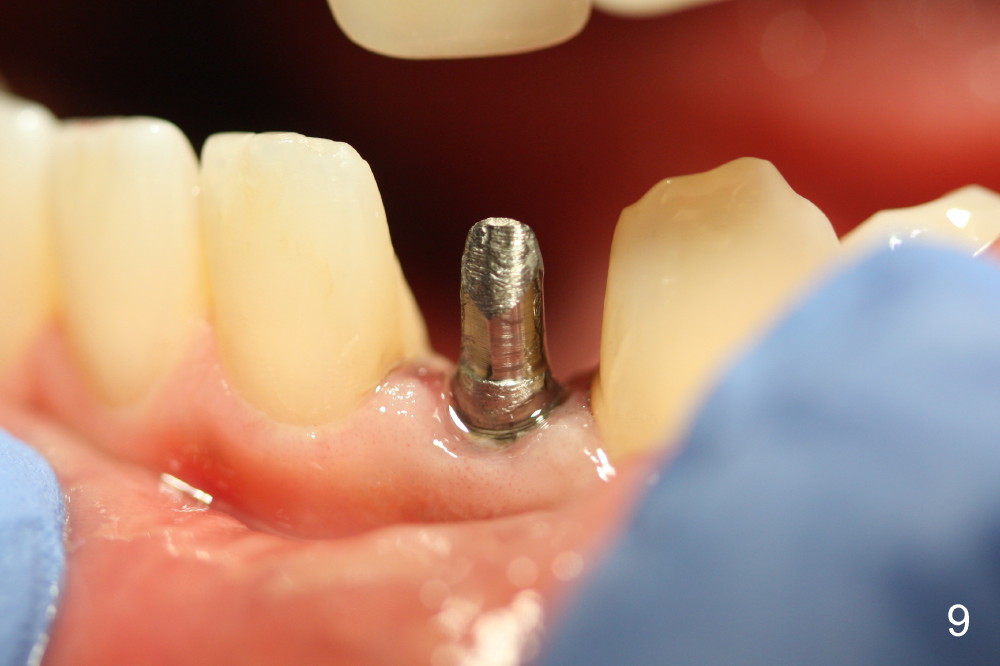

Within the first several days postop, the patient reports mild tenderness from one of the neighboring teeth. Otherwise she is doing fine. Again due to finance, she does not return for restoration for more than 1 year. PA taken 10 months postop shows that there is no abnormality (Fig.7). In fact bone resorption occurs gradually over 2 years 2 months postop, manifested as the 1st thread supracrestal (Fig.8 <). When the 1-piece implant is reprepped for impression 2 years 2 months postop, the micro threads are found apical to the prep margin (Fig.9). The nervous patient has had occasional tooth sensitivity 5 years postop. A narrower implant is more suitable for this case (2.0 or 2.5 mm).